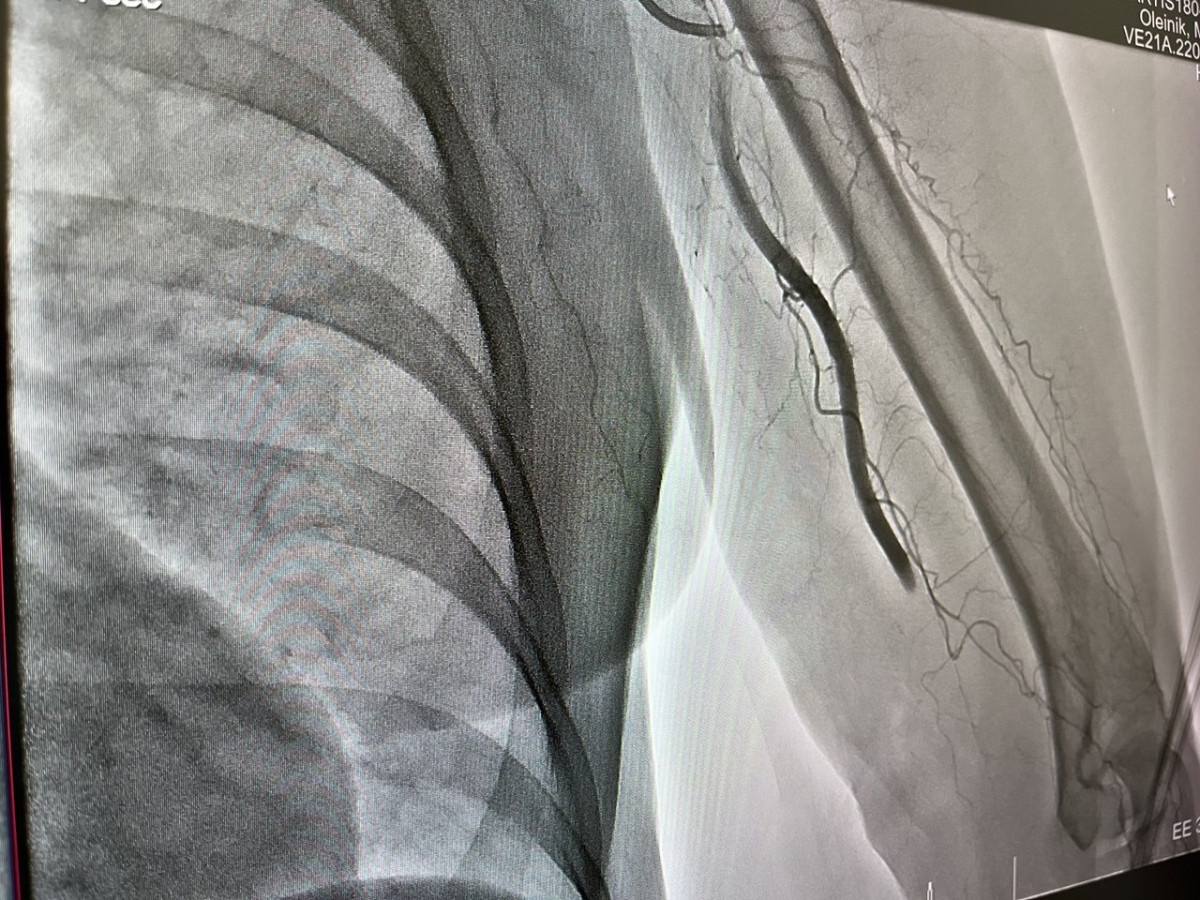

В Новокузнецке врачи городской клинической больницы №1 имени Г. П. Курбатова успешно удалили семисантиметровый тромб из артерии, спасая руку и жизнь пациентки. Об этом сообщил министр здравоохранения Кузбасса Андрей Тарасов в своем телеграм-канале.

Женщине стало плохо во время поездки в транспорте: сильная боль в руке привела к потере сознания. Ее экстренно доставили в больницу, где диагностировали тромбоз плечевой артерии левой руки. Нарушение кровообращения грозило ампутацией.

Врачи провели тромбэкстракцию - через бедренную артерию с помощью микрокатетера удалили закупорку. Кровоток восстановился практически сразу, жизнь и здоровье пациентки вне опасности.